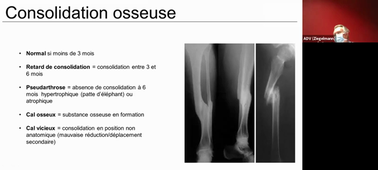

BO DFG3/DFA1 orthopédie 07/07/2021